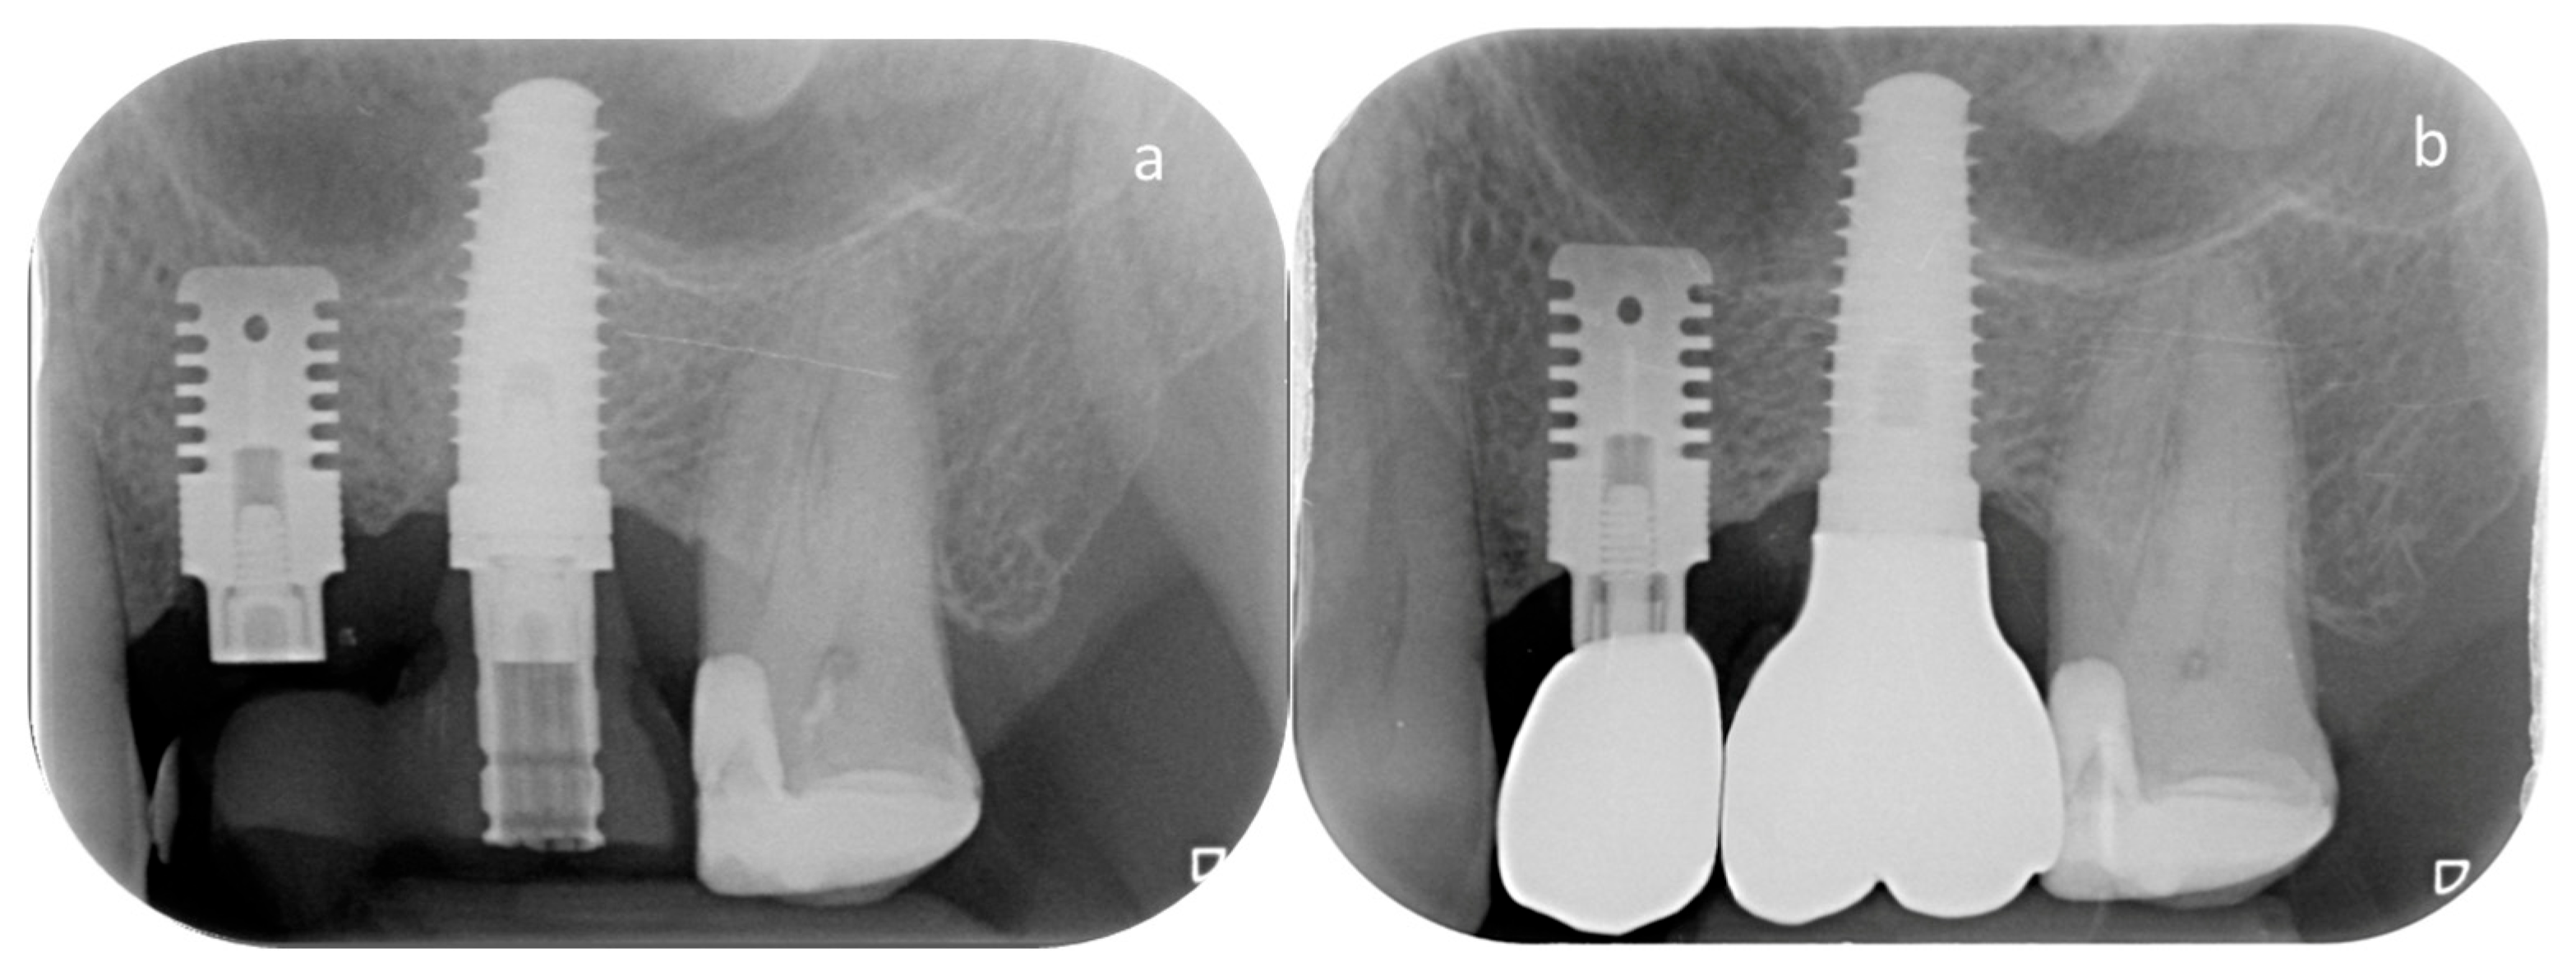

2.2. Implant Characteristics and Surgical Protocol

2.3. Clinical and Radiographic Evaluation